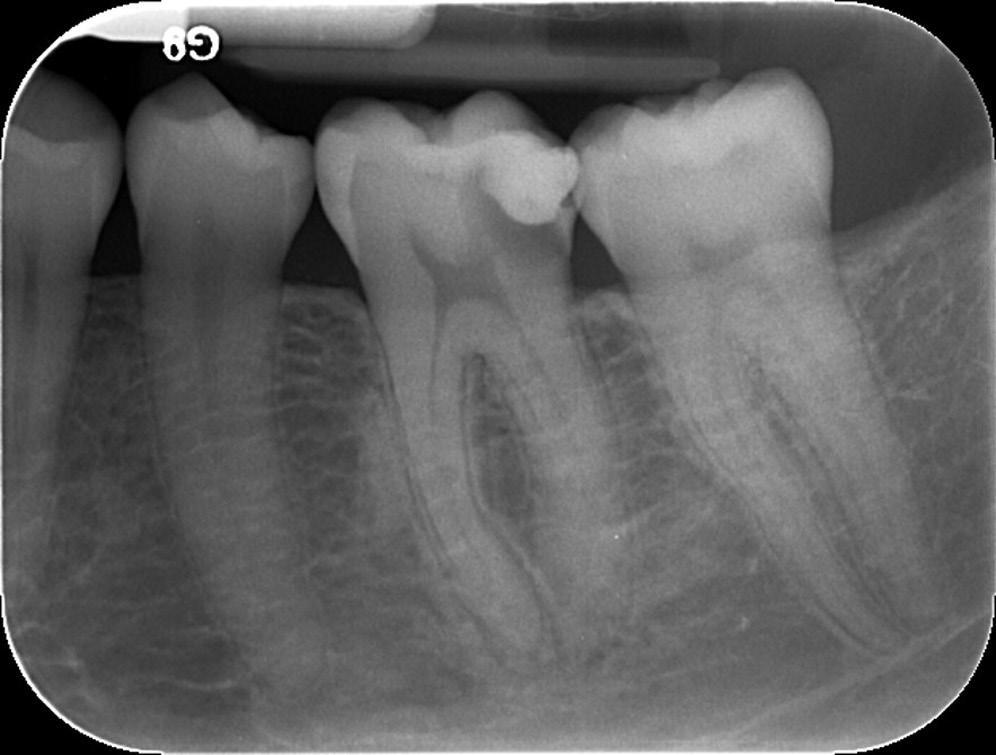

• Fig. 1.8 Radiograph showing pulp exposure as a result of caries.